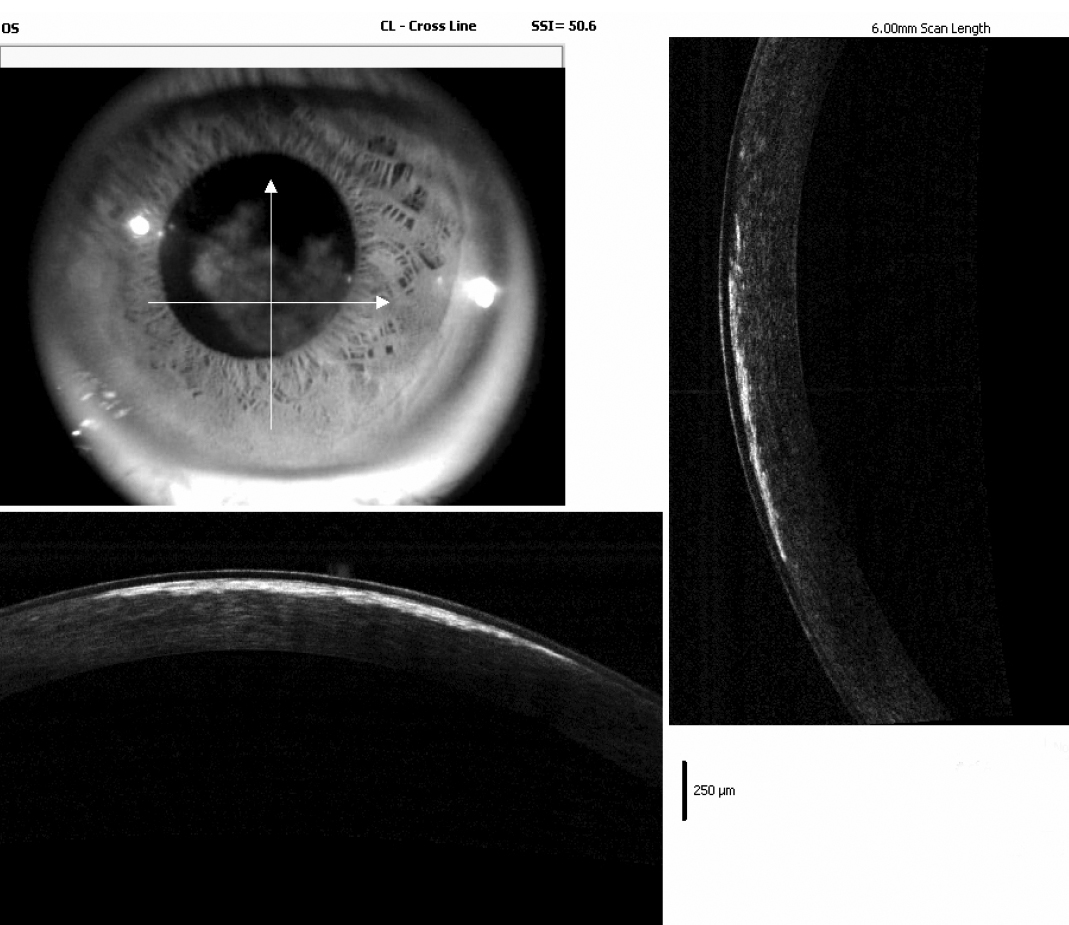

Figure 4. Fourier-domain OCT findings of the proband’s left cornea. Shown is the presence of crystalline deposits localized within the

anterior stroma in OS. The highest density of crystalline deposits seemed to be mainly in the anterior stroma, within the

first 100 µm of the corneal depth.